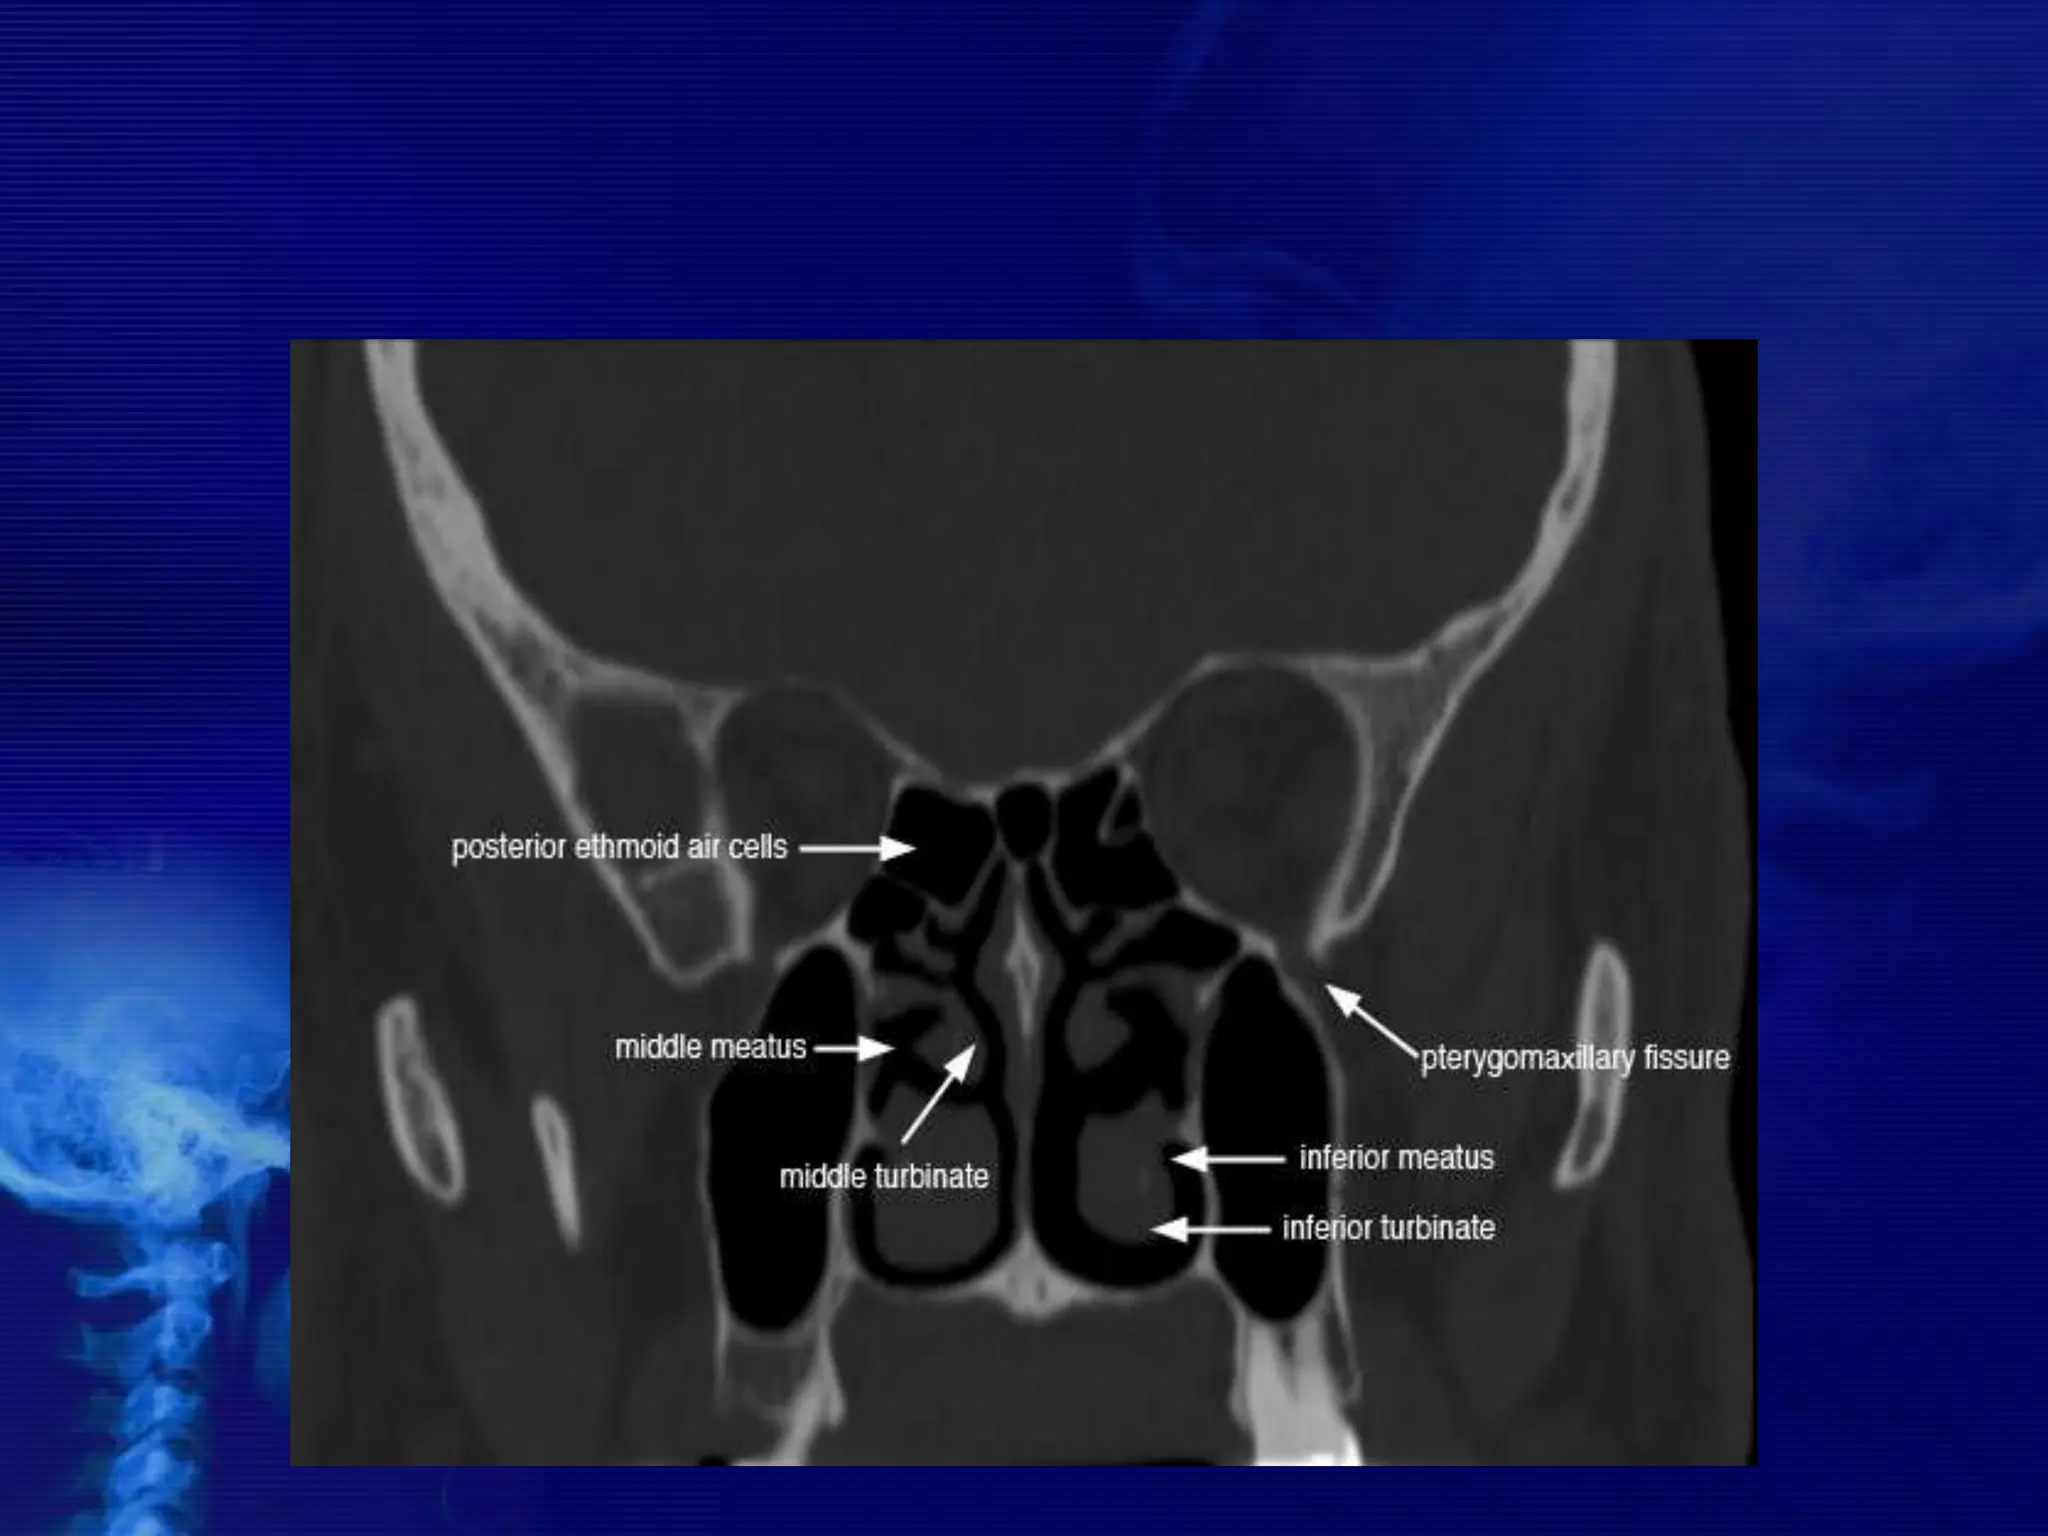

CORONAL ANATOMY

The Lateral Wall of Nasal Cavity

Marked by 3

projections:

• Superior concha

• Middle concha

• Inferior concha

• The space below

each concha is

called a meatus.

1. Inferior meatus:

nasolacrimal duct

2. Middle meatus:

• Maxillary sinus

• Frontal sinus

• Anterior ethmoid

sinuses

3. Superior meatus:

posterior ethmoid

4. Sphenoethmoidal

recess: sphenoid

sinus